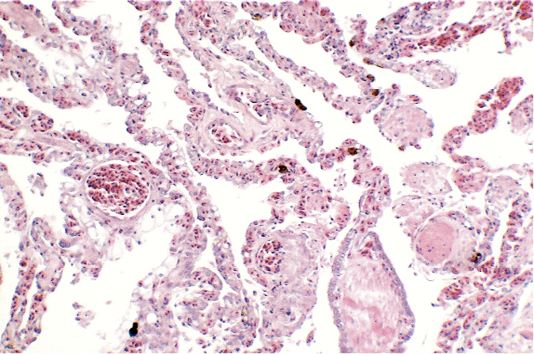

Lungs showing areas of extensive hyperaemia (H & E × 10, bar 100 μm).